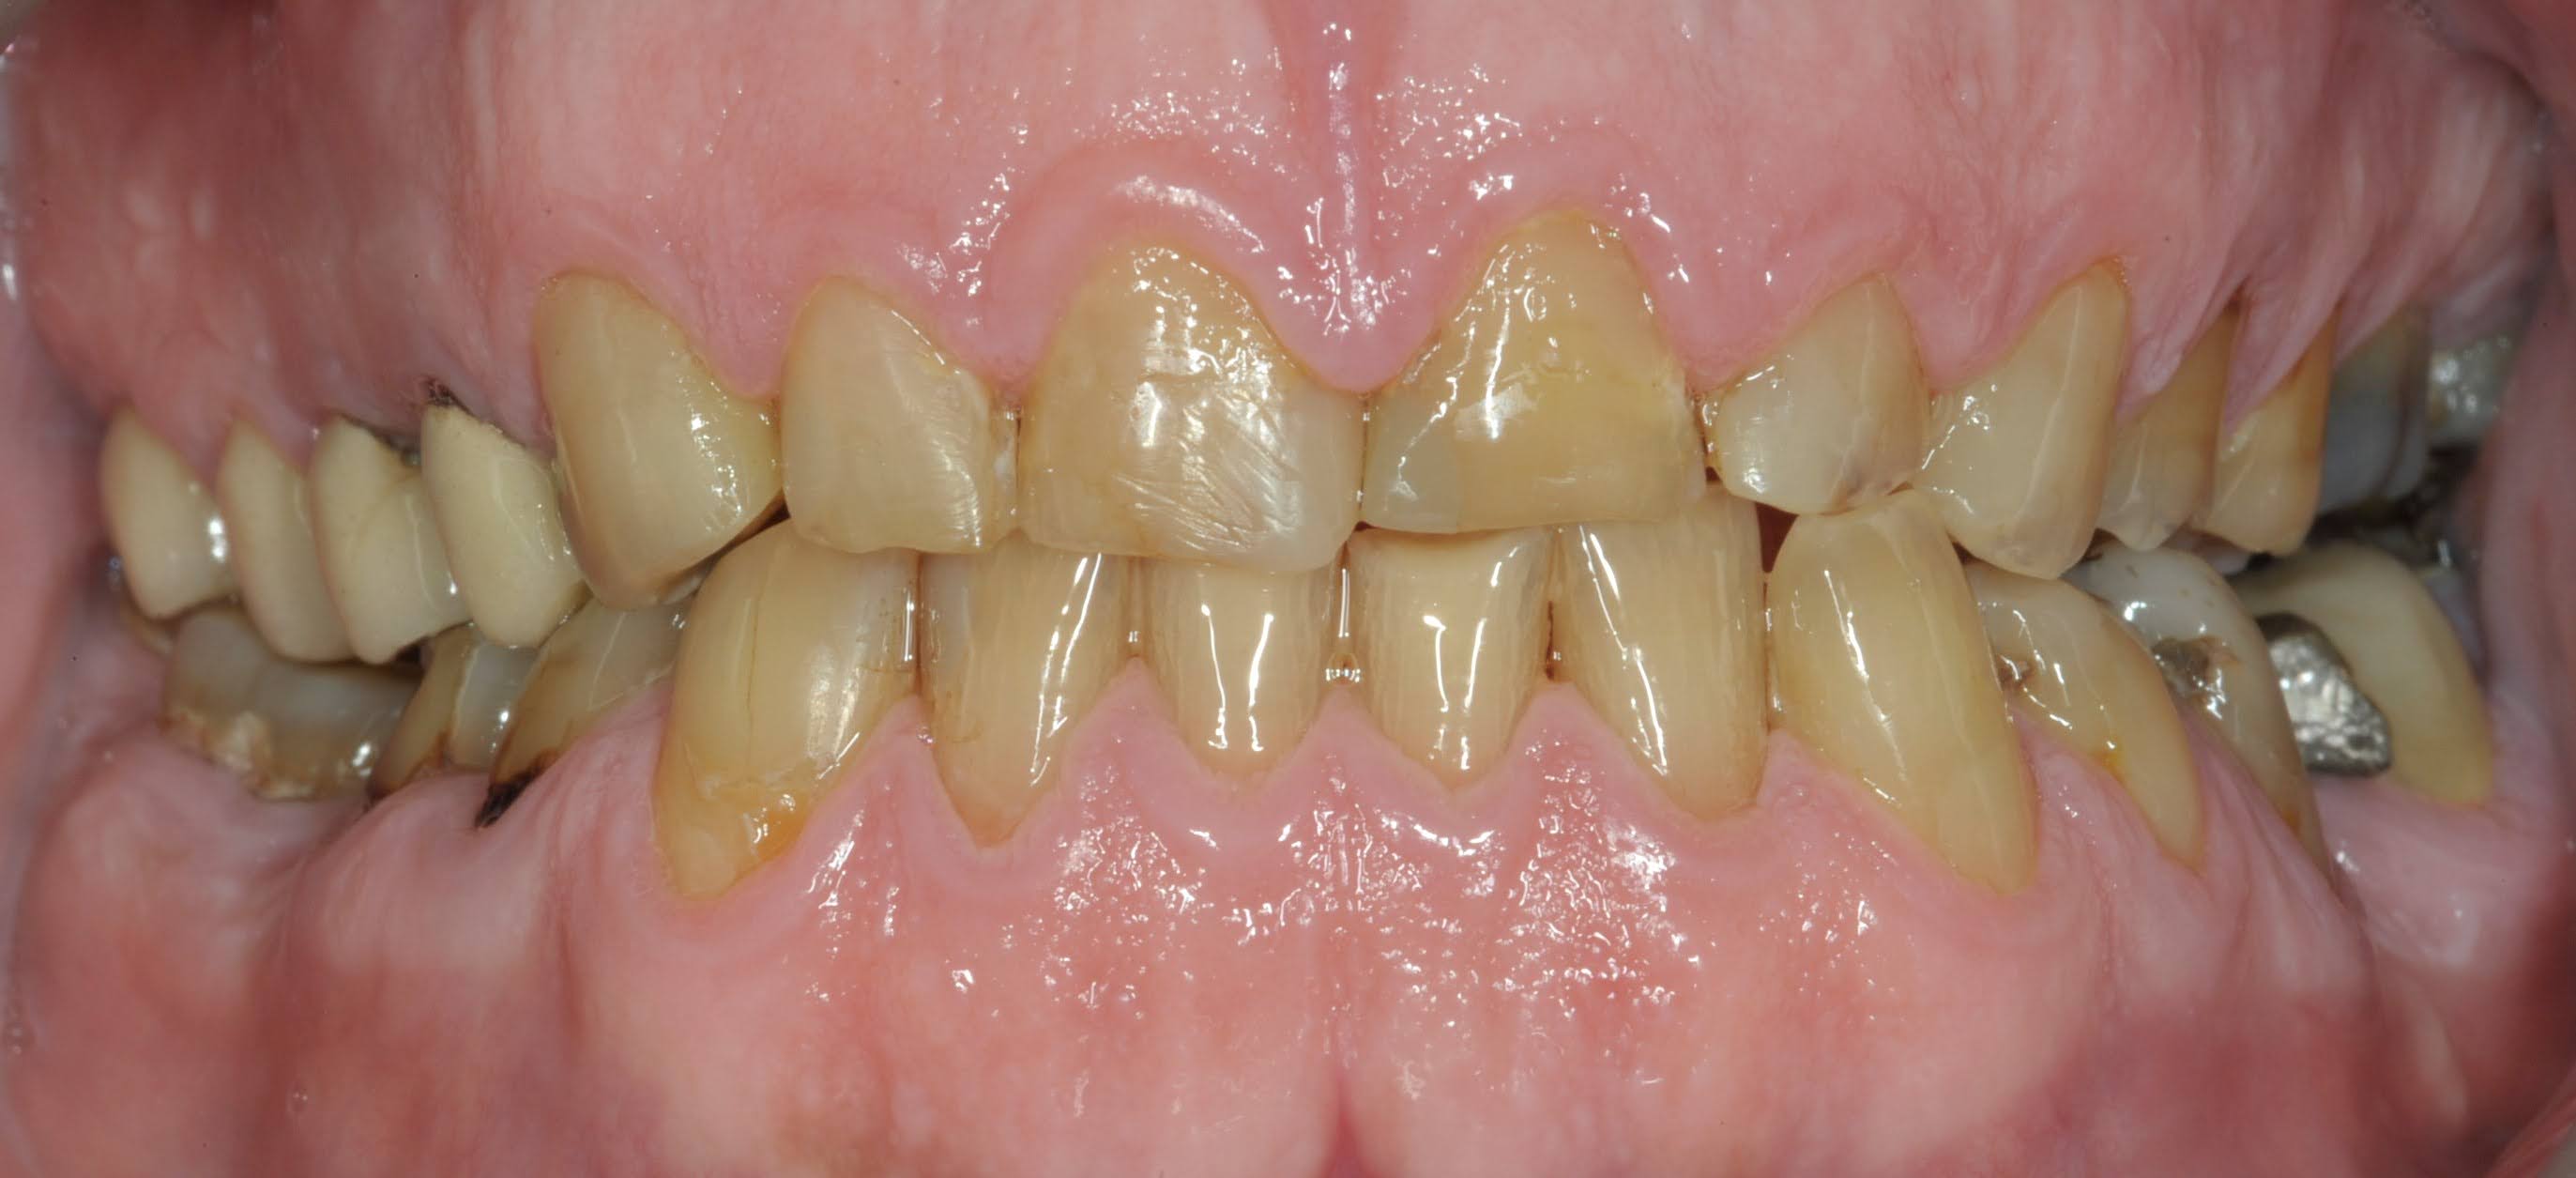

RMR

RMR - Antes RMR - Después

ANTES

DESPUÉS